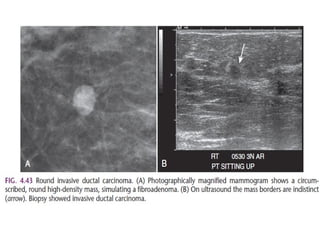

The shape of a mass is either round, oval or irregular.

The margin of a lesion can be:

Circumscribed (historically well-defined This is a benign finding.

Indistinct (historically ill-defined).

This is also a suspicious finding.

Spiculated with radiating lines from the mass is a very suspicious finding.

The density of a mass is related to the expected

attenuation of an equal volume of fibroglandular tissue.

High density is associated with malignancy.

Here a hyperdense mass with an irregular shape and a spiculated margin.

Notice the focal skin retraction.

This was reported as BI-RADS 5 and proved to be an invasive ductal

carcinoma.